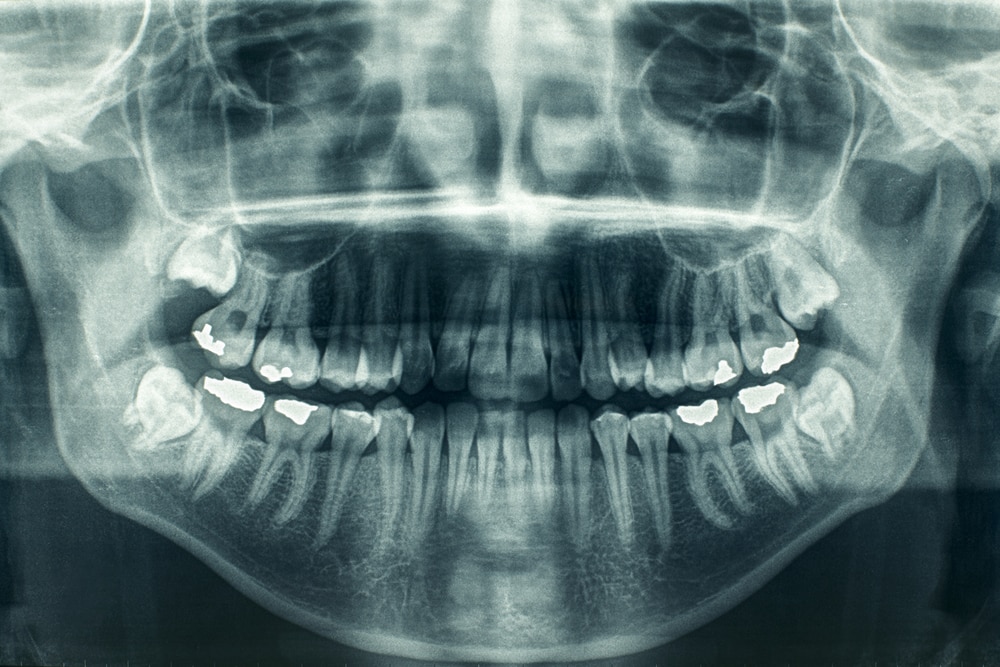

Стоматологические Исследования: Рентген Инвагинации Зубов